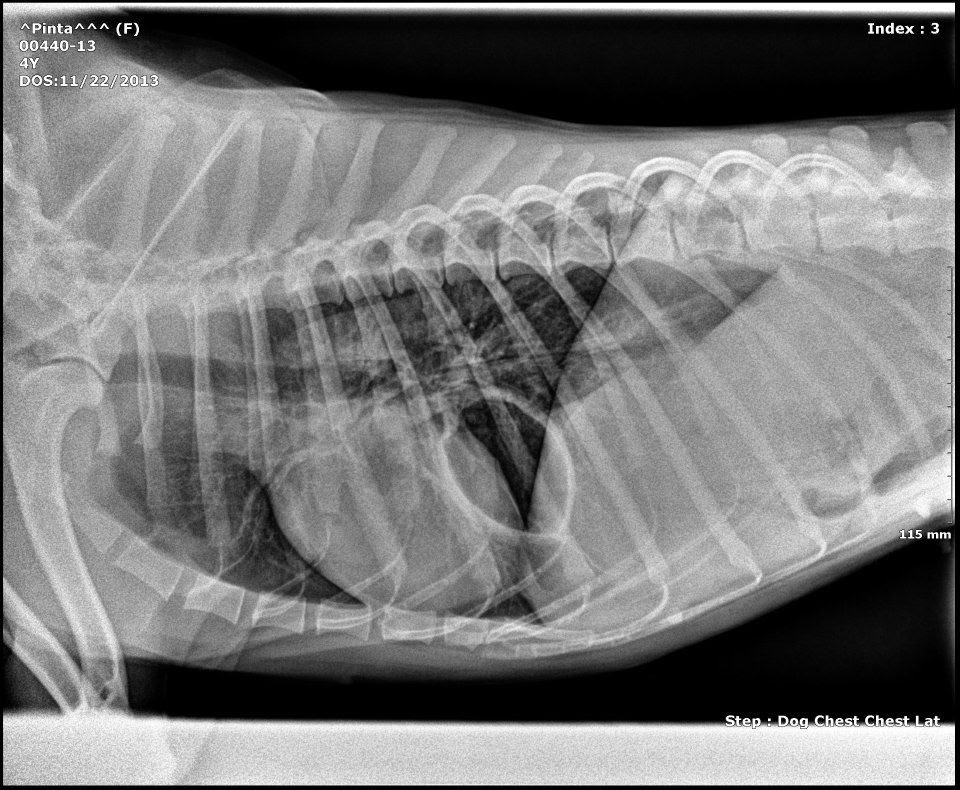

Clinica Veterinaria Dur-Can: Caso clínico de una hernia diafragmática

Source: veterinariadurcan.blogspot.mx